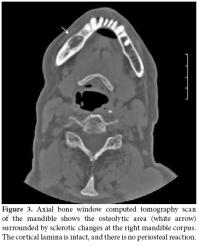

In September 2008, a 58-year-old female diagnosed with AS in 1973 was referred to Ege University Hospital, Department of Physical Medicine and Rehabilitation complaining of pain and discomfort in the right mandible. These symptoms had started in May 2008 following a tooth extraction. The extraction socket did not heal, even after eight weeks, despite antibiotherapy. Besides the pain and discomfort, she experienced the presence of some particles in the tooth extraction socket of her right mandible which were probably autogenous bone. A panoramic radiograph was taken 10 weeks later in July 2008 which revealed irregularity and diffuse sclerotic bone changes in the trabecular bone structure of the right mandible as well as a bony defect at the level of the extraction socket (Figure 1). A sample obtained from the exposed area was sent for culture to the microbiology laboratory due to the suspicion of dental infection/abscess. Oral flora microorganisms grew in the culture.

Together with the past history of long-term alendronate treatment and occurrence after tooth extraction, relevant clinical symptoms and conventional radiographic findings led to the suspicion of ONJ in this patient. We immediately ordered dental computed tomography (CT) which revealed sclerosis and osteolytic changes in the right mandible. This confirmed the diagnosis of osteonecrosis (Figures 2, 3). The patient also consulted with dental surgeons, and since there was no pathologic fracture, extra-oral fistulae, or osteolysis extending to the inferior border of the mandible, the disease was accepted to be in the second stage. Surgery was not recommended, and conservative management was started. The patient was advised to discontinue the alendronate treatment, and the etanercept treatment was also stopped. A good oral hygiene regimen using antibacterial tooth rinse was recommended. Her complaints and symptoms alleviated gradually. A control panoramic radiography taken after one year of bisphosphonate withdrawal displayed healing of the exposed bone (Figure 4).